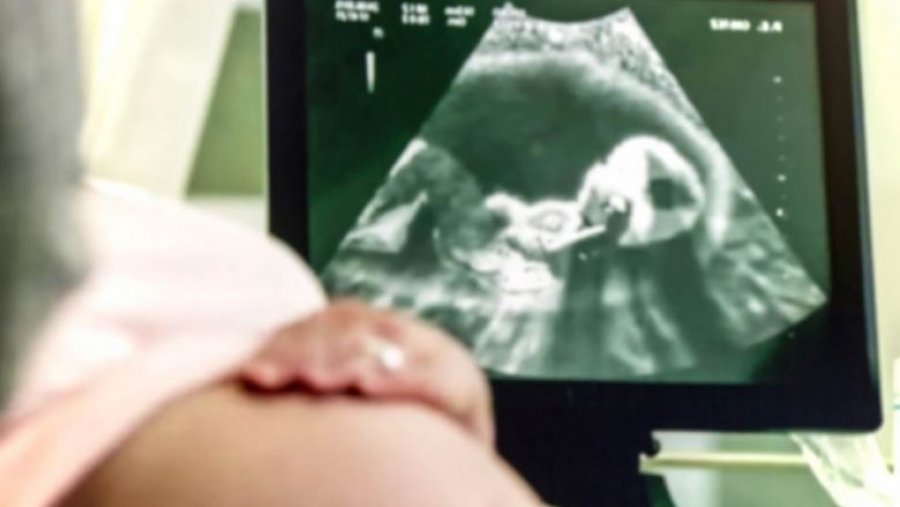

Kur bëhet fjalë për zhvillimin e të parit te bebet, ato fillojnë të shohin dritën në muajin e dytë, por rreth javës së 28-të të shtatzënisë mund të hapin dhe t’i mbyllin sytë në mitër. Duket magjepsëse, apo jo?

Nëse drejtoni një elektrik dore në barkun tuaj shtatzënë, bebja do të trazohet dhe ju mund t’i ndieni ato lëvizje, por ajo që ju nuk mund të shihni dhe ajo që mund të regjistrojë ultrazëri është se foshnja do të mbyllë njërin sy në atë moment. Kjo mund të jetë loja e parë e saj.

Në imazhin e ultrazërit, shikoni si mbyll njërin sy bebja në stomak, transmeton Telegrafi.